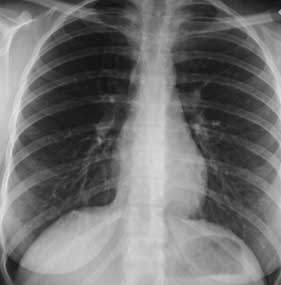

Pour s'y retrouver dans la radio, il faut savoir qu'il y a différents contrastes naturels :

air < graisse < eau < os < métaux (prothèse, plombages)

Pour faire simple, l'air, dans les poumons ou les intestins par exemple, va apparaitre très noir, et les métaux très blancs. (voir sur la photo).